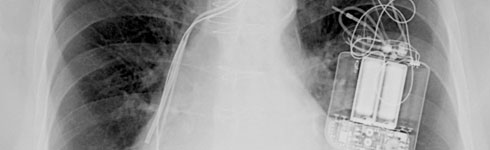

Cardiac Pacemaker

Many people who have an abnormal heart rhythm run the risk of sudden death if that heart rhythm gets out of control. A cardiac pacemaker can significantly reduce the risk of sudden death by providing a small, controlled electric current when needed to maintain steady rhythm.